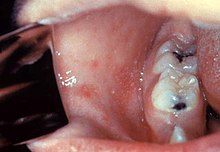

Les signes pathognomoniques sont très rares, ce qui fait toute la difficulté du diagnostic médical. Le plus connu est le signe de Koplik, qui consiste en la présence de petites taches blanchâtres sur la muqueuse buccale en regard des molaires, qui surviennent quelques jours avant l'éruption de la rougeole.

- Le signe de Koplik est classiquement considéré comme pathognomonique de la rougeole, à connaitre pour un diagnostic pré-éruptif précoce de la rougeole[4], cependant quelques études récentes en contestent le bien fondé : ce signe pouvant se voir dans d'autres affections virales comme la rubéole, ou le parvovirus B19[5],[6].